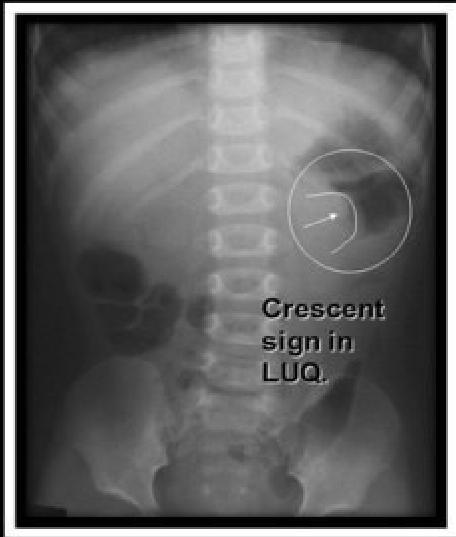

- X-ray â density in the area of the intussusception â crescent sign.

X-ray

- â Crescent sign